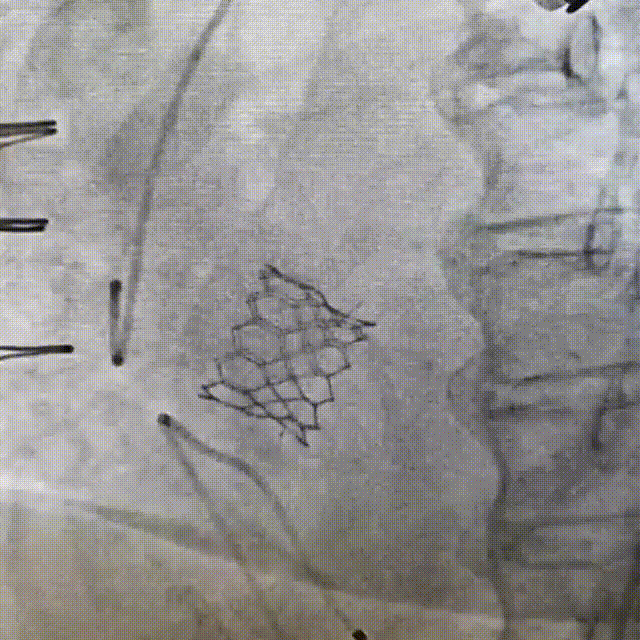

Imagem da Semana

Belo resultado de uma angioplastia de tronco de coronária esquerda após valve-in-valve aórtico em paciente com alto risco de oclusão do tronco pela prótese (altura de 5 mm da prótese).